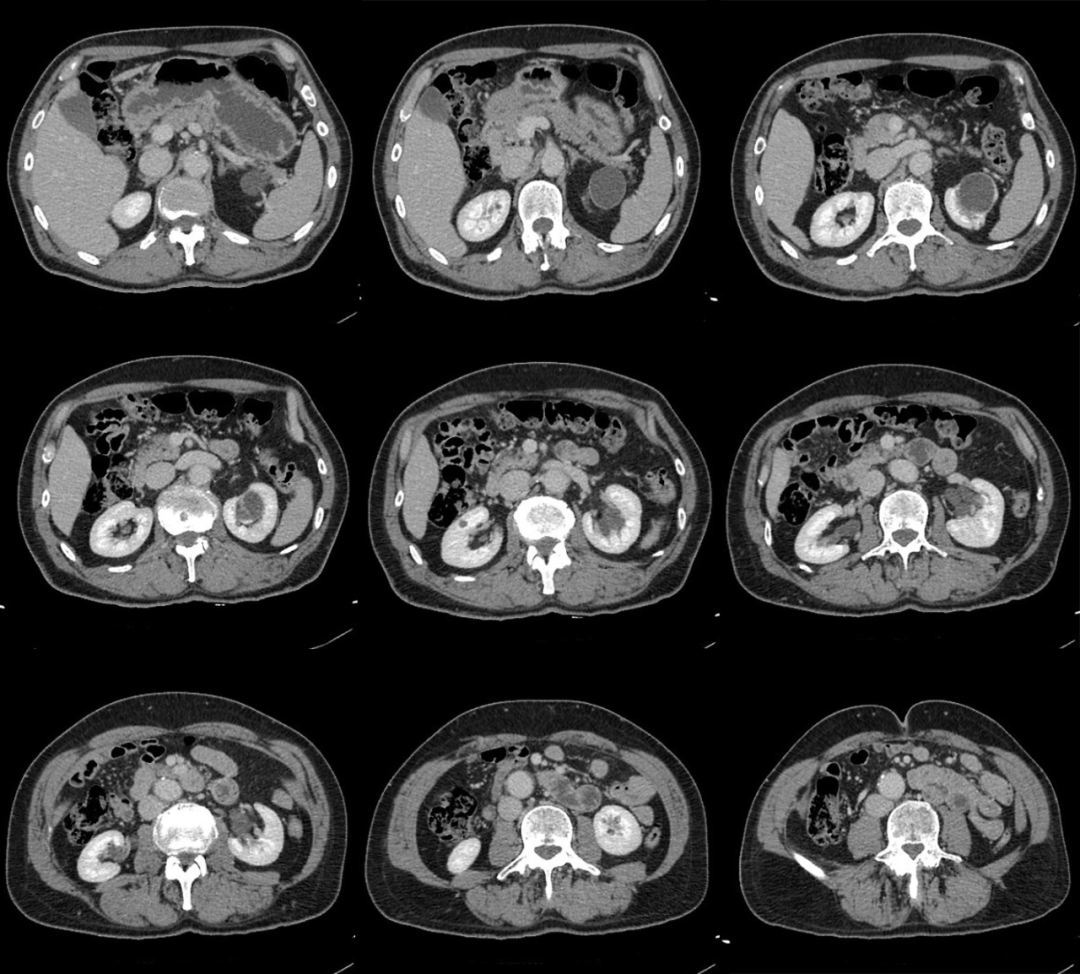

患者男性 43 岁 因左侧腰背部疼痛不适,左侧腰背部叩击疼阳性,门诊拟:「 肾结石 」 行 CT 检查;

咦!没有发现明显的阳性结石啊,就左肾囊肿;

嗯,真的就是囊肿嘛?

我们建议 CT 增强扫描;

动脉期

静脉期